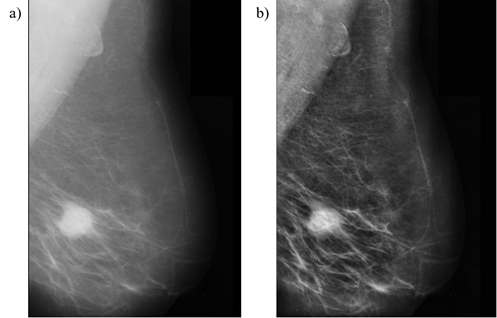

Con la finalidad de obtener un mayor número de anotaciones, se procedió a realizar una aumentación de datos, al aplicar la técnica de Ecualización Adaptiva de Histograma por Limitación de Contraste (CLAHE) sobre las mamografías y sus lesiones o regiones de interés (ROI); en la Figura 3, se observa la basta mejora sobre la mamografía al aplicar la técnica CLAHE [15], siendo que se pueden observar de mejor manera las estructuras de la mama.

Figura 3. Mejora de la mamografía CLAHE, a) Mamografía original, b) Mamografías tras aplicar CLAHE